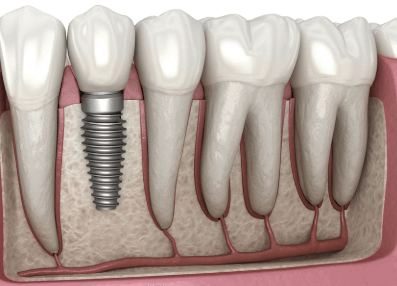

치아가 튼튼한 건 정말 큰 복입니다. 오복 중 하나이기도 하고요. 임플란트 하기 전에 꼭 알아야 할 중요 고려사항에 어떤 것들이 있는지 체크해보세요. 수술 후 회복기간은 얼마나 걸리는지, 반드시 지켜야 할 관리방법에 대해서도 살펴보시기 바랍니다.

임플란트 시술 시 중요 고려사항

1) 시술 경험과 치과 선택 : 임플란트는 고난이도 시술이므로 경험이 많은 치과를 선택하는 것이 중요합니다. 3D CT 촬영, 디지털 가이드 시스템 등 첨단 장비를 갖춘 곳이 유리합니다.

2) 사용되는 임플란트의 브랜드 및 품질 : 국내 브랜드(오스템, 덴티움)와 해외 브랜드(스트라우만, 노벨바이오케어 등) 중 선택할 수 있습니다. 브랜드마다 가격과 내구성이 다르므로 치과에서 어떤 제품을 사용하는지 확인해야 합니다.

3) 비용과 추가 치료 여부 : 임플란트 1개당 평균 비용은 120만 원~300만 원 정도이며, 추가 뼈 이식이 필요한 경우 비용이 증가합니다. 사전 상담 시 전체 비용(크라운 포함) 을 정확히 확인하는 것이 좋습니다.

4) 잇몸뼈 상태와 건강 상태 : 잇몸뼈가 부족하면 뼈 이식이 필요하며, 당뇨병·골다공증 환자는 치료가 제한될 수 있습니다. 수술 전 기본 건강 상태를 체크해야 하며, 흡연자는 회복 속도가 느릴 수 있습니다.

5) 사후 관리 및 보증 기간 : 임플란트는 10~20년 이상 유지할 수 있지만, 정기적인 관리가 필수입니다. 일부 치과에서는 평생 보증 서비스를 제공하므로 보증 기간을 꼭 확인하세요.